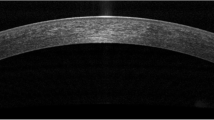

Corneal imaging in health and dry eye disease. a Horizontal OCT section of the normal human cornea showing the epithelium, Bowman’s membrane, stroma, Descemet’s membrane and endothelium. In vivo confocal micrographs (IVCM) of the cornea in normal and dry eye subjects (b–g). b Normal superficial epithelium showing regularly arranged cells with dark nuclei. c Superficial epithelium in dry eye disease showing squamous metaplasia, hyperreflectivity, and lower cell density as compared to normal. d Subbasal layer showing normal corneal nerve plexus and dendritic cells. e Subbasal layer in dry eye with increased density of dendritic cells. f Reduced density of nerves. g Hyperreflective and tortuous nerves. IVCM image: magnification: ×800

Principles of anterior segment optical coherence tomography (AS-OCT)

Optical coherence tomography (OCT) is a non-contact in vivo imaging method that incorporates the principle of low-coherence interferometry to generate cross-sectional images of ocular tissues and its microstructures [201]. AS-OCT permits near-histological visualization and biometry of the anatomical structures starting from the tear film, corneal epithelium, stroma, endothelium, corneo-scleral junction, sclera, anterior chamber, trabecular meshwork, irido-corneal angle, anterior pigment of the iris, and anterior capsule of the lens, making it an indispensable tool for clinical and surgical management of anterior segment pathology [202–211].

Methods of signal acquisition and processing determine features of the OCT such as speed of imaging and resolution of the images. Based on these technical differences in design, the two most popular types of commercially available OCT for anterior segment imaging are time-domain OCT (TD-OCT), such as the Visante omni and Visante OCT (Carl Zeiss, Meditec Inc.) [212, 213], and spectral-domain OCT (SD-OCT), available as slit-lamp OCT (SL-OCT, Heidelberg Engineering, Vista, CA, USA), and more recently, the Envisu C-class (Bioptigen, Durham, NC, USA) [214–216]. Moreover, the RTVue OCT (Optovue) with the anterior segment cornea module provides high-resolution anterior segment imaging. Technical features of these two techniques with respect to AS-OCT are listed in Table 1.

The ultra-high resolution OCT (UHROCT), which has a lateral resolution of 10 μm, is also used extensively for in vivo corneal and anterior chamber imaging in ophthalmic practice [217–219]. It provides good tissue penetration, resolution for diagnostic assessment, and the ability to use images for 3D reconstruction [220]. Quantitative parametric and volumetric analysis of the cornea and lacrimal functional unit becomes possible with the UHROCT.

AS-OCT in the diagnosis and assessment of therapy in dry eye